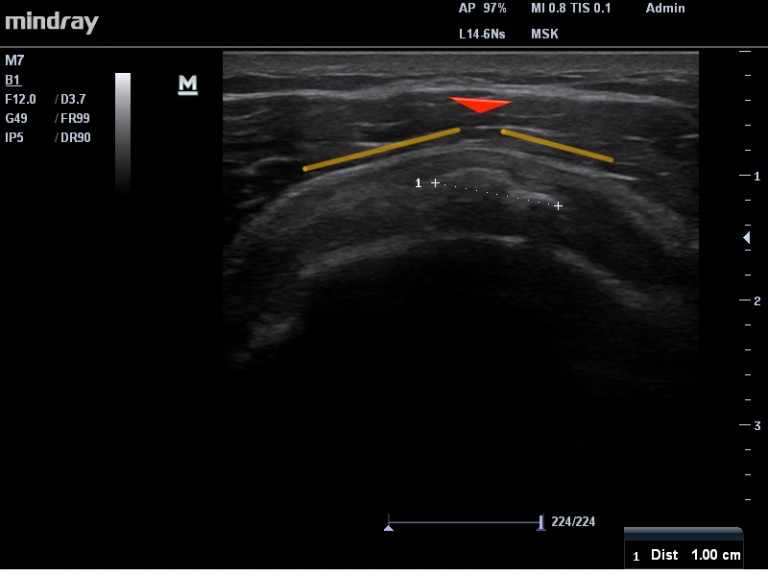

LA PHASE FORMATIVE, est certainement la phase où nous recevons le plus de patients en consultation. Très clairement : plus la calcification est volumineuse (> 1cm) et plus elle déforme le tendon ( Images 1 et 2) donc plus le risque d’avoir une épaule douloureuse est important.  Les douleurs peuvent durer des mois , voire des années, si le patient non traité,  n’a pas la « chance » d’avoir une résorption spontanée. Il existe toute une série de traitements possibles lors cette phase :

Image 2. Calcification de type 2, en cours de traitement. Amélioration symptomatique du patient. La structure de la calcification change, la déformation tendineuse est moins importante.